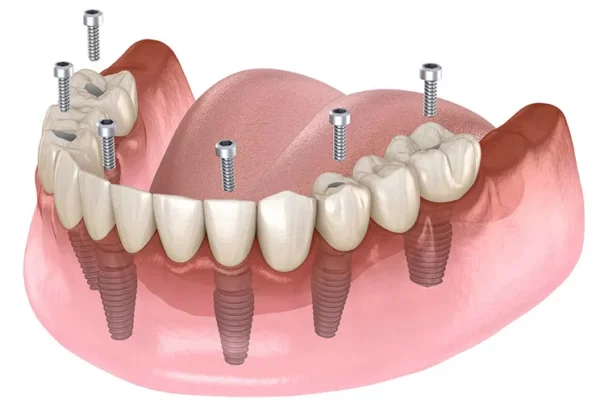

All on Four ve All on Six İmplant

Tamamen dişsiz veya kalan dişleri çekilmesi gereken hastalar için tek bir operasyonda ve tek bir protez ile sabit dişlere kavuşma imkanı sunan yenilikçi çözümlerdir. Hızlı iyileşme ve yüksek konfor sunar.

3) All-on-Four / All-on-Six bana uygun mu?

Tam dişsizlikte tek aşamada sabit proteze geçiş için iyi seçeneklerdir. Kemik hacmi, sistemik durum, sigara alışkanlığı ve hijyen motivasyonu değerlendirilir. Geçici–kalıcı protez zamanlaması hastaya özelleştirilir.